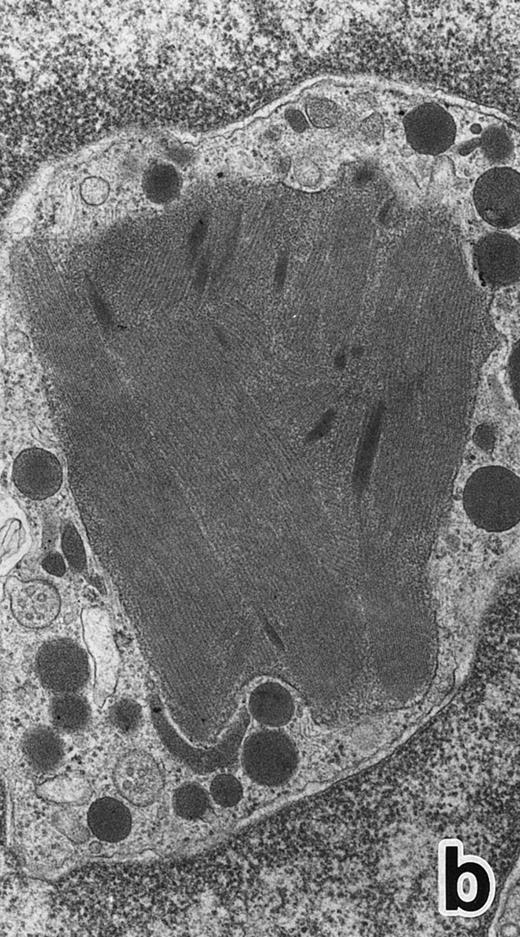

Bone marrow leukemic cells in patient no. 1 at diagnosis (a), after 1 week of ATRA treatment (b), and after 3 weeks of ATRA treatment (c). (Original magnification × 330.)

After 2 to 3 weeks of ATRA treatment, maturation of leukemia cells progressed further, and cells resembling normal PMNs appeared (Fig 5). These cells contained multilobulated nuclei with marginally condensed heterochromatin and glycogen particles, characteristic of normal mature neutrophils. rER and free ribosomes became rare as the maturation process proceeded. However, these cells were still rich in primary (type I) granules, which somewhat varied in size and shape, including small and/or elongated forms. A small number of ellipsoid type II primary granules with a nucleoid structure were occasionally observed in patients no. 1 and 2, but not in patient no. 3. Conversely, MPO-positive, small, possibly type III, primary granules were rarely observed intermingled among the larger primary granules in maturing neutrophils in patient no. 3 alone. Despite the ultrastructural features otherwise characteristic of normal mature PMNs, specific granules, which are electron-lucent, elongated or dumbbell-shaped small granules, were not present in the majority of these PMN-like cells, as clearly shown by electron-microscopic cytochemical staining for MPO (Fig 5). The cells contained only MPO-positive primary granules and no MPO-negative secondary granules. A few abnormal primary granules, including Auer rods or C-H type granules, were still present in some cells, and these cells too were consistently devoid of specific granules (Fig 6). Another unusual finding in PMN-like cells at this stage was the presence of large spherical lipid droplets (Fig 5a), which may indicate altered physiological metabolism in these cells,29 because lipid droplets are usually not seen in normal PMNs. Although few in number, PMNs having both primary and secondary granules were also observed (Fig 7), and less mature intermediate forms with indented single nuclei or irregularly lobulated nuclei and numerous primary granules were still present at this stage of ATRA treatment.